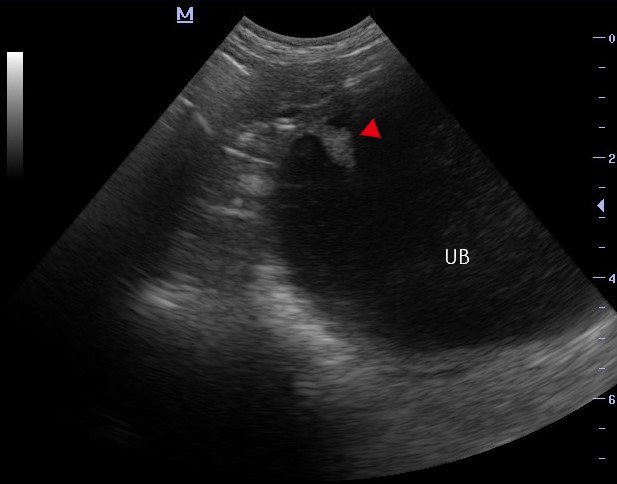

Polypoid cystitis is an uncommon condition and can appear as a hyperechoic mass or masses protruding from the wall into the lumen of the bladder. These occur most commonly on the cranioventral aspect of the bladder (Figure 6). 6 However, as bladder neoplasia is more common, immobile masses attached to the bladder wall via a pedicle or wide base should be characterised through histological diagnosis only.

Figure 6. Polypoid Cystitis – A pedunculated hyperechoic mass (arrow) arising from the ventro-cranial wall and projecting into the lumen of the urinary bladder (UB).